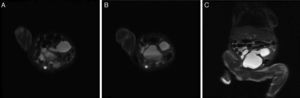

Ecografia obstétrica. Corte coronal del feto, en el que se observa una imagen quística de pared gruesa, comunicada con lo que pareciera corresponder a la vejiga; se sospecha megauréter y megavejiga. Nótese el líquido libre en cavidad abdominal. En la evaluación retrospectiva, las imágenes quísticas observadas probablemente correspondían al cuello uterino (a la derecha de la imagen) y al útero (a la izquierda), distendidos por material mucoide.